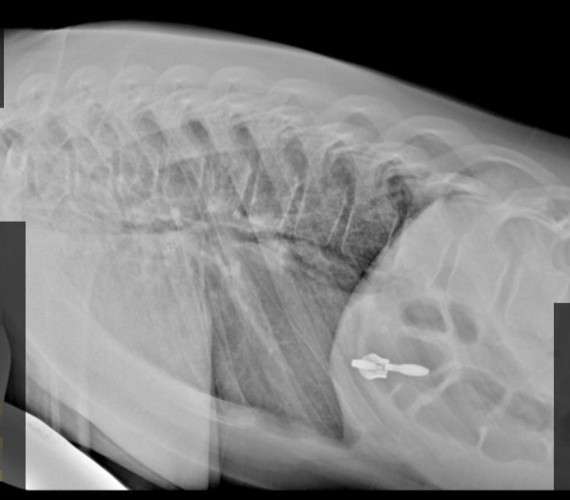

За одни сутки пять детей поступили в травмпункт Ивано-Матрёнинской детской клинической больницы в Иркутске с компрессионными переломами позвоночника. Все пациенты, кроме одного, попали в стационар.

Специалисты называют этот случай нерядовым, так как обычно пациенты с такой травмой поступают далеко не каждый день, сообщает пресс-служба ИМДКБ.

Один из пострадавших получил перелом, упав на гололёде, двое —прыгая на батутах в развлекательных центрах и ещё двое — при занятиях спортом.